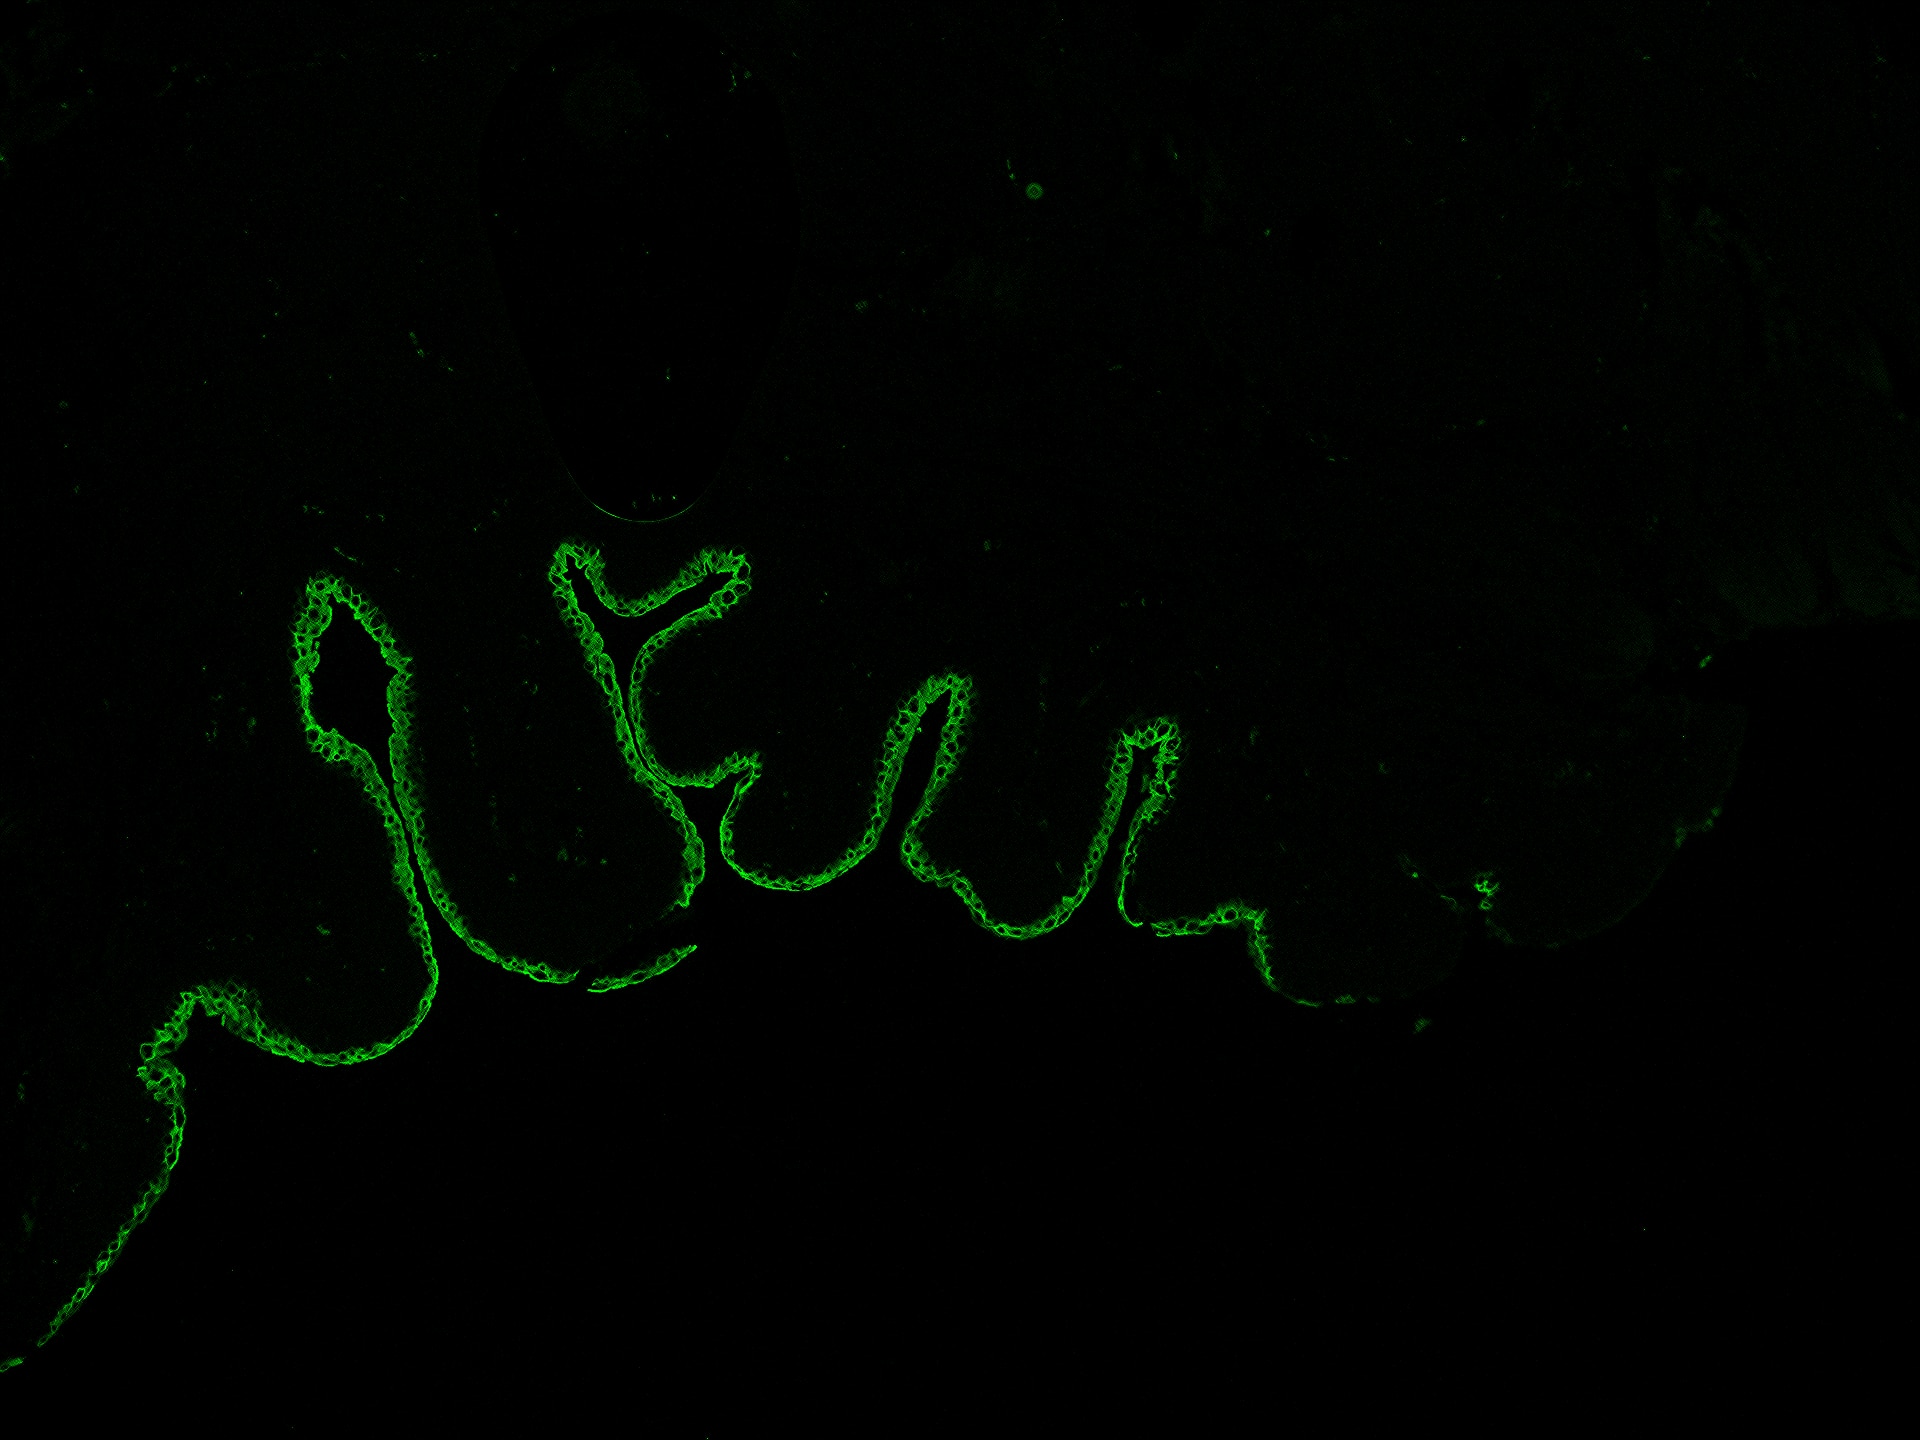

Enlarge |

Affinity Purification | Canine | 03/08/2022 |

| Verified Customer 03/08/2022 |

| Application: | Affinity Purification | |

| Species: | Canine |